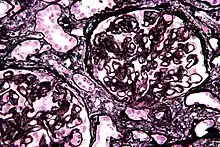

Micrograph of membranous nephropathy showing prominent glomerular basement membrane spikes. Jones' stain.

• By light microscopy, the basement membrane is observed to be diffusely thickened. Using Jones' stain, the GBM appears to have a "spiked" or "holey" appearance.